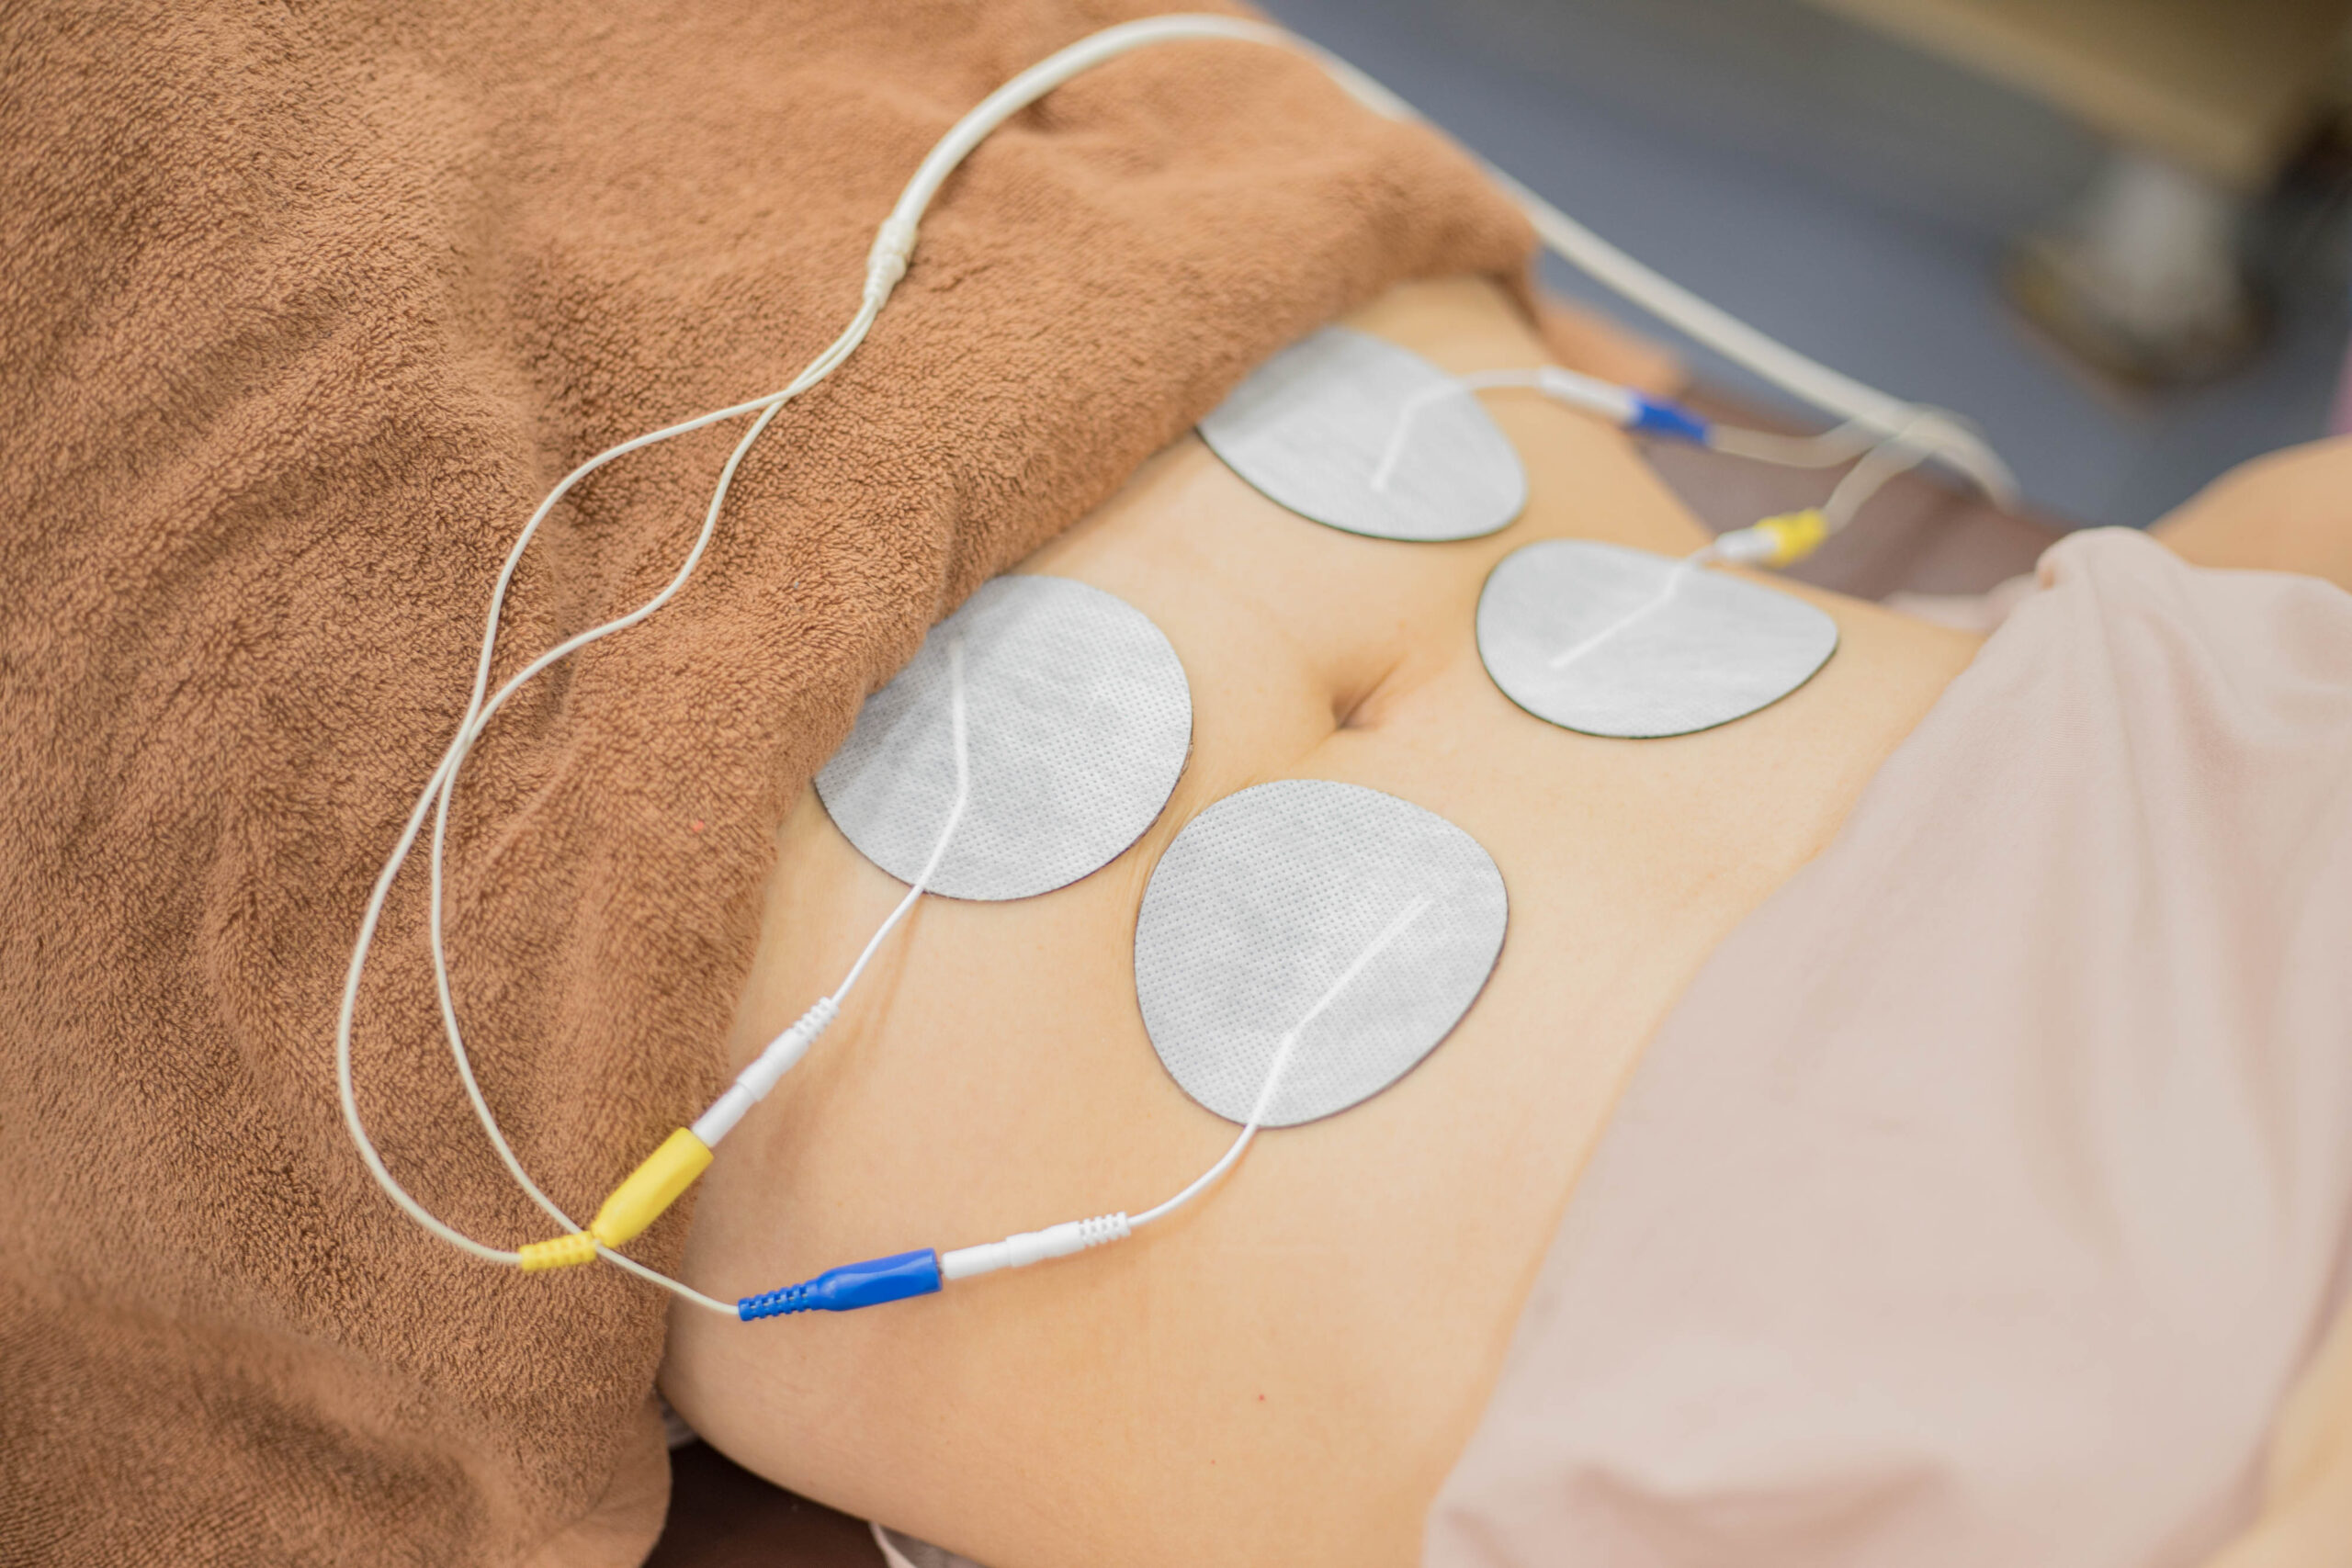

そこで当院では検査を行い、インナーユニットに原因がある場合はハイボルト療法やCMC筋膜ストレッチ、トレーニング指導を行います。

また、自律神経に原因がある場合は炭酸ヘッドスパ(THS)やHOT腸もみ、CMCはり施術などホルモンバランスや体内リズムを整える施術を行います。